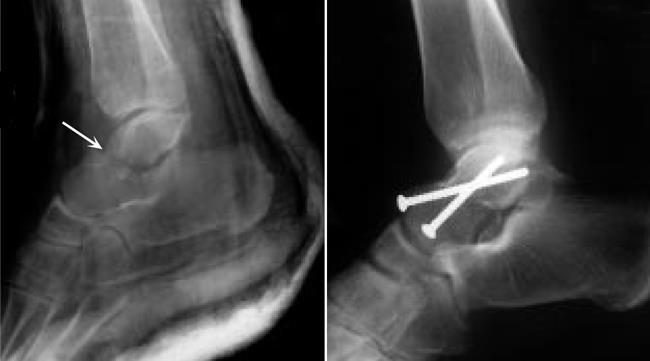

1. fibular malleolus fracture

거의 항상 high ankle sprain이 있음.

tibia -fibular를 고정한 이유는 anterior tibiofibular ligament(high ankle sprain)가 손상을 입었기 때문. 6주후에 tibia-fibular를 고정한 나사는 제거해야 함. 4-6주동안 체중부하를 주면 안됨.

6주이내에 full ROM 회복해야 함.

plate는 1년 후 제거함.

생체역학 : tibia에 체중부하 83%, fibular에 17% 체중부하.